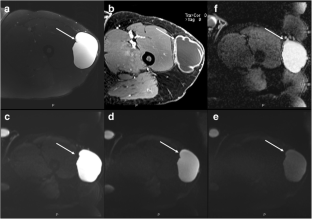

Fig. 1

Fig. 2

Fig. 3

Fig. 4

Fig. 5

Fig. 6

Fig. 7

Fig. 8

Fig. 9

Fig. 10